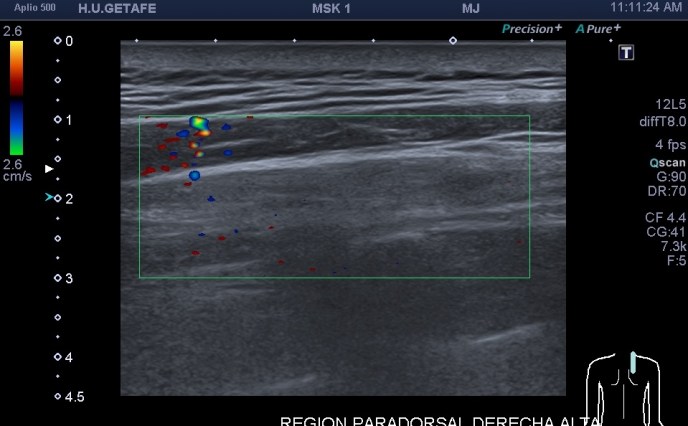

4.Tendón del infraespinoso

En el final del protocolo tenemos el infraespinoso. En relación con este corte te voy a contar que es un corte donde estudiamos en normalidad, articulación glenohumeral, labrum posterior (triangular e hiperecogénico), músculo infraespinoso como puedes ver en las dos imágenes siguientes, donde existe normalidad en la primera y donde coexiste la anatomía con la patología por la ausencia del labrum, sustituido por una buena cantidad de líquido justo en la articulación glenohumeral.